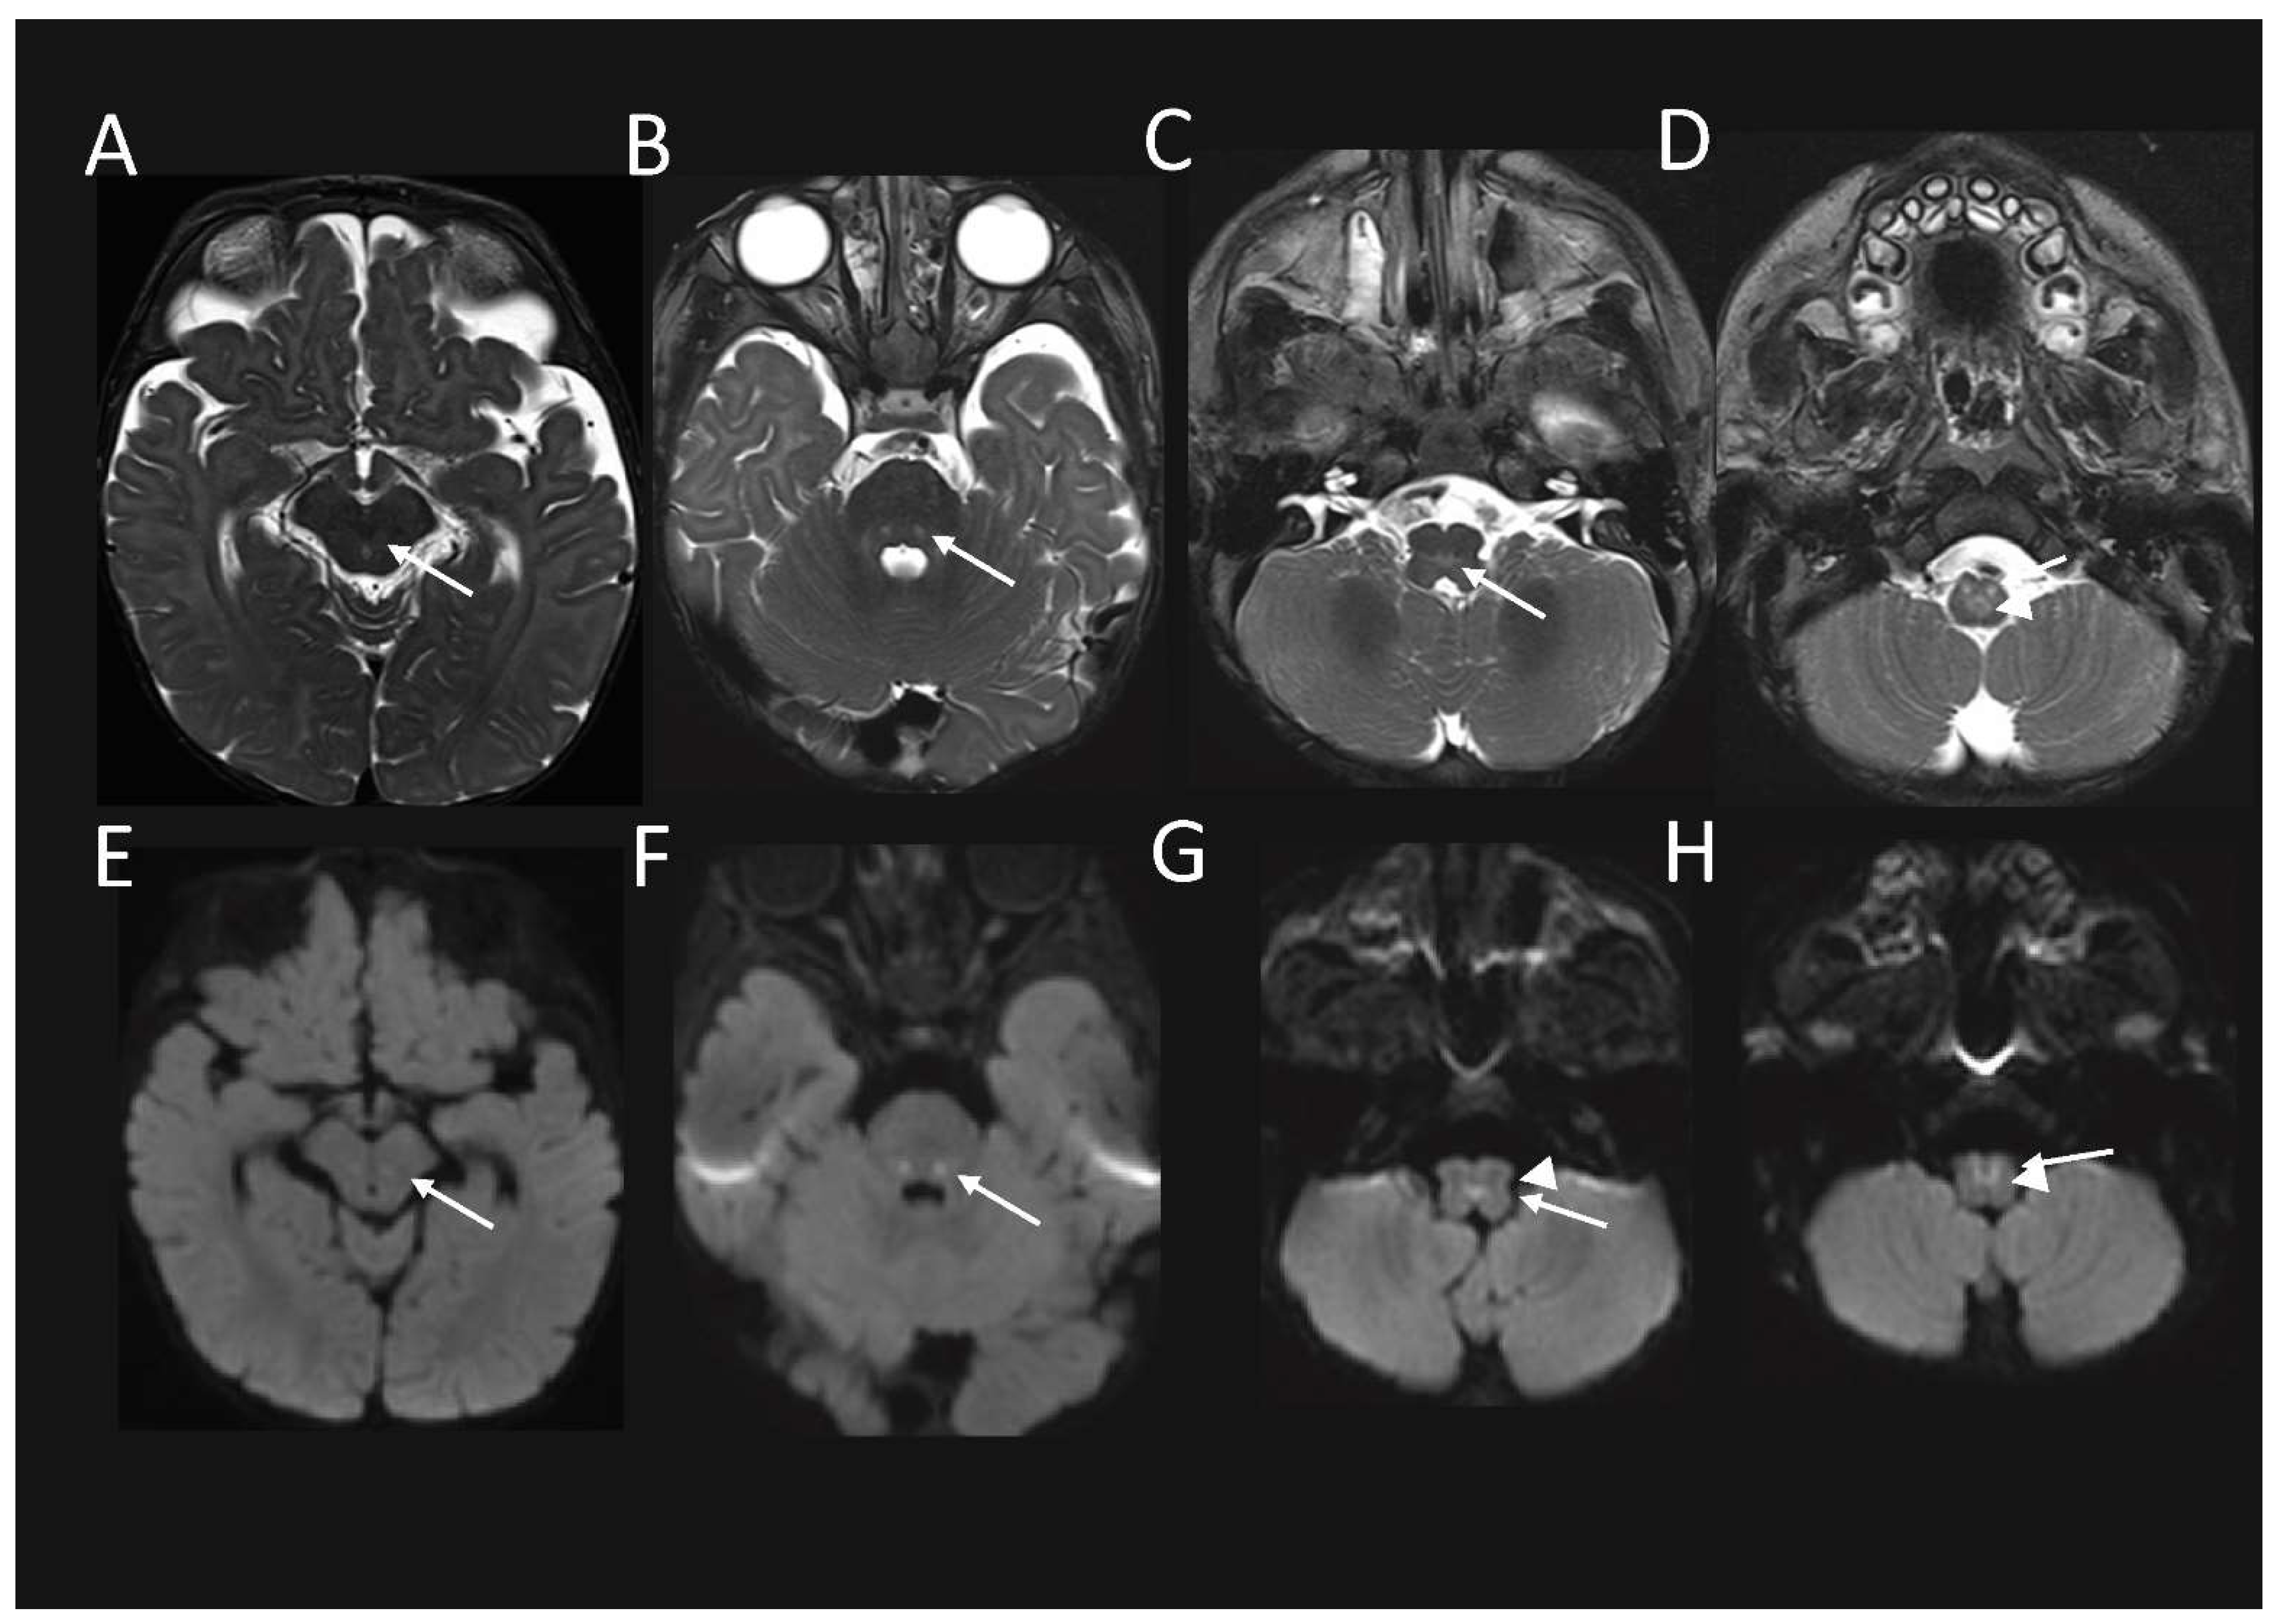

The p.(Gly426Ser) missense variant is present in exon 12 of the PYROXD2 gene and is predicted to be disease-causing by MutationTaster, and probably damaging (score of 0.994) and deleterious by PolyPhen-2 and SIFT analysis, respectively. This variant is present in gnomAD V2.1.1 with a global allele frequency of 8.41 × 10−6, with two heterozygous individuals of European (non-Finnish) ancestry and no homozygous individuals reported. The p.(Gly426Ser) variant lies within a highly conserved (Phast cons score of 0.997, Phylop score of 3.734) region of the protein, predicted to be an amino-oxidase domain of the protein (Figure 3A). The variant has not previously been published in the literature or relevant variant databases (ClinVar, HGMD public, DECIPHER, LOVD). RNAseq analysis confirmed the missense variant was expressed in the proband (Supplemental Figure S1C), in approximately 50% of the observed reads. The presence of the variant in the paternal RNA sample could not be confirmed due to the insufficient read depth.

The second variant introduces a change from valine to cysteine at codon 498 of the protein, followed by a frameshift that introduces a premature stop-codon 79 amino acids downstream. As the variant is located in the last exon of the PYROXD2 gene (Exon 14), it is predicted to escape non-sense mediated decay (NMD). Although there are no reported domains in this region, this would represent a significant alteration to ~15% of the protein and may result in significant 3D structural alterations in the regions highlighted in the wild-type protein structure (Figure 3B). The regions affected by the frameshift variant include a beta strand and two alpha helices (Figure 3C). Consistent with NMD escape, the frameshift variant was observed in the RNASeq data (Supplemental Figure S1D) in both the proband and the mother, in approximately 50% of the reads. The overall PYROXD2 expression levels were not significantly decreased compared to the controls. Furthermore, RT-PCR and qPCR showed normal levels of the PYROXD2 transcript (Supplemental Figure S2), and Western blotting demonstrated normal levels of the PYROXD2 protein (Supplemental Figure S3). The variant was present in gnomAD V2.1.1 with an allele frequency of 3.98 × 10−6, with one heterozygote individual of European (non-Finnish) ancestry and no homozygote individuals reported. The variant has not previously been published in the literature or relevant variant databases (ClinVar, HGMD public, DECIPHER, LOVD).

Figure 3. Evolutionary sequence conservation and 3D structure of PYROXD2. (A) The multiple sequence alignment of PYROXD2 reveals the affected p.Gly426 residue is highly conserved. (B) The predicted 3D structure of wild-type PYROXD2 (AF-Q8N2H3-F1, AlphaFold, modelled in icn3d) highlighting the patient variant p.(Gly426Ser) is highlighted in yellow, and the wild-type residues affected by the frameshift variant p.(Val498Cysfs*79) are highlighted in red. (C) Structural regions (from icn3d) indicate that the frameshift variant starting at p.Val498 (region highlighted in yellow) affects a beta-fold region (amino acids 498–504) and two major alpha-helical regions (amino acids 506–513 and 565–578) of the PYROXD2 protein.